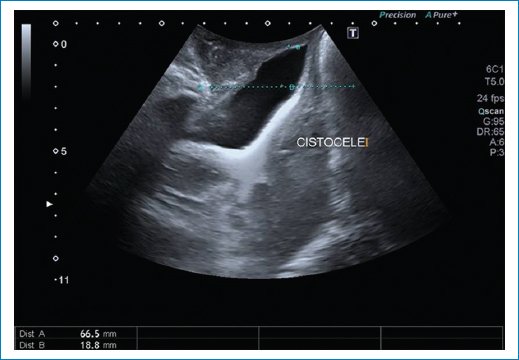

• – Cistocele: con el examen físico solamente podemos evaluar un prolapso de la pared anterior de la vagina; sin embargo, con las imágenes podemos diferenciar entre un cistouretrocele que se asocia a incontinencia de orina y un cistocele con ángulo retrovesical intacto con síntomas de obstrucción al vaciado y baja probabilidad de incontinencia de orina. También puede ser que el prolapso de la vagina anterior sea por un divertículo uretral, quiste de Gartner o un enterocele anterior. El punto de corte para determinar el descenso de la vejiga es 10 mm por debajo de la línea pubiana que se traza perpendicular a la sínfisis pubiana3 (Fig. 7).

Figura 7. Se observa un descenso de la pared posterior vesical por debajo de la línea pubiana, con ángulo retrovesical cerrado.